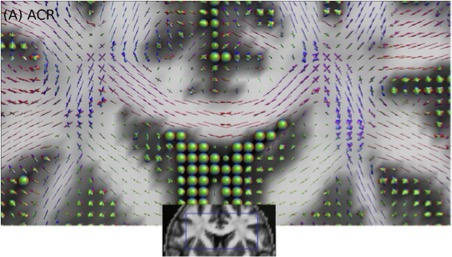

The LTS5 Diffusion group focuses on brain tissue microstructure and structural connectivity –estimated by diffusion Magnetic Resonance Imaging (dMRI) data, with a particular focus on the reconstruction of the nerve fiber orientation distribution function (ODF) per voxel (see the figure below). This information is important for the reconstruction of the brain’s white matter by using fiber tracking algorithms (see ref [1]).

The LTS5 Diffusion group focuses on brain tissue microstructure and structural connectivity –estimated by diffusion Magnetic Resonance Imaging (dMRI) data, with a particular focus on the reconstruction of the nerve fiber orientation distribution function (ODF) per voxel (see the figure below). This information is important for the reconstruction of the brain’s white matter by using fiber tracking algorithms (see ref [1]).

We have implemented various novel reconstruction algorithms (e.g., see refs. [2-5]) and we plan to develop a new generation of methods using Machine Learning techniques. The goals of this project are: (1) create a large database of fiber ODFs and corresponding dMRI signals, (2) Design, train, and optimize a neural network using this dataset, (3) predict the fiber ODFs from new dMRI data, and (4) compare the implemented algorithm with state-of-the-art techniques using both synthetic and real dMRI data acquired from human brains. The results will be published in international conferences and relevant journals.